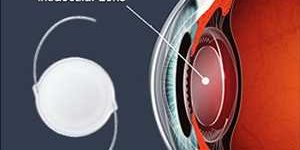

Demanda del mercado mundial de lentes intraoculares, pronóstico de ingresos y oportunidades interesantes de 2022 a 2028

Zion Market Research ha publicado el último informe sobre el » mercado Lente intraocular » global. Los detalles sobre el mercado Lente intraocular se han actualizado completamente con información completa …